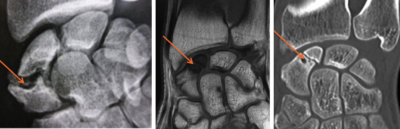

Radio, IRM et scanner d’une pseudarthrose du scaphoïde

Le bilan comprend :

- des radiographies du poignet,

- un scanner permettant de mieux caractériser la déformation,

- une IRM permet d’étudier la vascularisation du scaphoïde,

- un arthro-scanner.